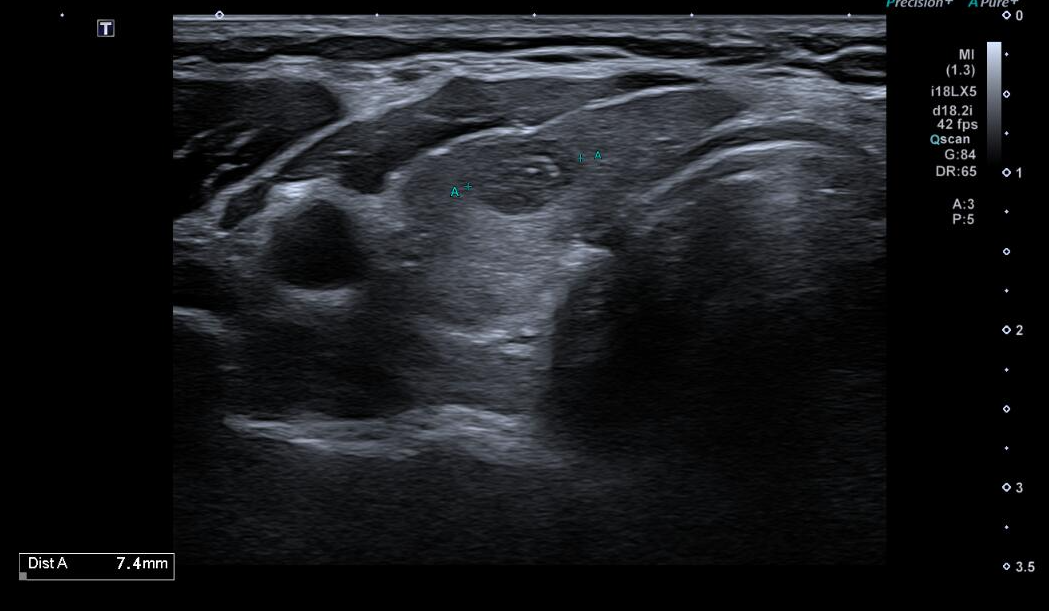

Tras dichos hallazgos, se decide realización de Ecografía Clínica.

Ecografía clínica:

Ecografía reglada (Servicio de Radiología):